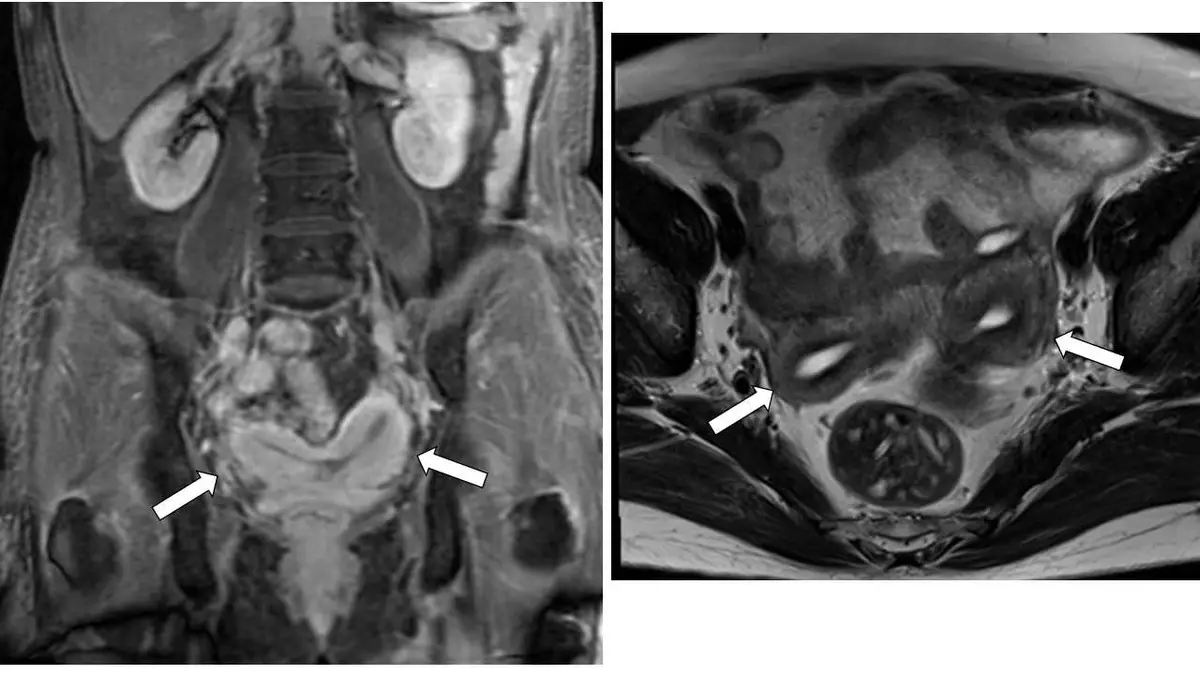

本題提供兩張骨盆 MRI 影像(冠狀位 + 軸位):

左圖(冠狀位 coronal view):

- 可見子宮基底部(fundus)呈明顯凹陷/分叉形態,形成兩個分開的子宮角(uterine horns),箭號分別指向左右兩個子宮角。

- 兩角之間可見子宮底的外輪廓向內凹陷(fundal cleft),凹陷深度 > 1 cm。

- 兩角之間在中下段仍有子宮肌層(myometrium)相連,顯示兩角有部分融合,這與雙子宮(uterus didelphys)不同。

- 整體外形呈「心形(heart-shaped)」子宮底。

右圖(軸位 axial view):

- 兩白色箭號指向兩側子宮角的橫切面,兩角清楚分離。

- 兩角之間角度增寬(intercornual angle > 105°),符合雙角子宮的診斷標準。

- 兩角中間可見連接的子宮肌層組織。

影像診斷結論:外輪廓呈心形凹陷、兩個分開但下方相連的子宮角、fundal cleft >